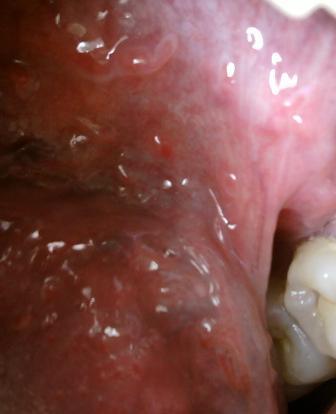

石家庄尖锐湿疣医院治疗尖锐湿疣的方法是什么现在治疗尖锐湿疣的方法是比较多的,但是每一种治疗方法在治疗上都是有自己的优缺点的,对此建议大家在选择治疗方法的时候不可以盲目,而是应该去正规的医院在主治医师的指导之下,根据自身病情选择适合自己的治疗方法,任何疾病只有经过正规的治疗才可以达到很好的治愈疾病的目的。尖锐湿疣是一种人类乳头瘤病毒,传染性是比较强的,但是感染上病毒之后,一般不会立即发病,而是一般有三个月的潜伏期,潜伏期是没有任何明显的症状表现的。